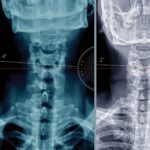

Desalineación espinal

Misalignment